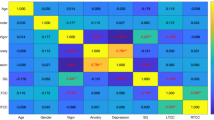

To determine whether the topological properties and nodal FC were correlated with the severity of sleepiness in the narcolepsy patients, a partial correlation analysis was performed to evaluate the relationship between sleepiness severity (ESS, mean sleep latency, and mean REM sleep latency from the MSLT) and topological properties in brain regions or nodal functional connectivity between ROI seeds showing significant differences between groups, adjusted for gender, age, and BMI. Partial correlation analysis was performed using the IBM Statistical Package for the Social Sciences 23.0 software (IBM SPSS Inc.) with a significance level at P < 0.05.

Sparsity values were selected in the analysis of nodal topological properties. Many brain nodes showed altered topological properties between narcolepsy patients and healthy controls. Specifically, eight overlapping nodes – the bilateral inferior frontal gyrus (IFG), right anterior cingulate gyrus (ACG), left supplementary motor area (SMA), right calcarine fissure (CAL), and bilateral basal ganglia – had the same alterations in centrality measurements (BC and DC) in patients and controls (Fig. 3 and Table 3). Meanwhile, six overlapping nodes – the left IFG, left ACG, left posterior cingulate gyrus (PCG), bilateral posterior central gyrus (PoCG), and left caudate (CAU) – had the same alterations in clustering measurements (NCC and NE) in patients and controls (Fig. 4 and Table 3).

Eight overlapping regions in centrality measurements (BC and DC) and their functional connectivity in comparisons between healthy controls and narcolepsy patients. Scatter plots and partial correlation analysis between nodal topological or functional connectivity and severity of sleepiness in narcolepsy. FC, functional connectivity; ESS, Epworth Sleepiness Score; IFG, Inferior frontal gyrus; ACG, anterior cingulate gyrus; CAU, caudate nucleus; PUT, putamen; PAL, pallidum; SMA, supplementary motor area; CAL, calcarine fissure; L, left; R, right.

Six overlapping regions in clustering measurements (NCC and NE) and their functional connectivity in comparisons between healthy controls and narcolepsy patients. Scatter plots and partial correlation analysis between nodal topological or functional connectivity and severity of sleepiness in narcolepsy. FC, functional connectivity; ESS, Epworth Sleepiness Score; IFG, inferior frontal gyrus; ACG, anterior cingulate gyrus; CAU, caudate nucleus; PCG, posterior cingulate gyrus; PoCG, postcentral gyrus; L, left; R, right.

Partial Correlation Analysis

In the graph theoretical analysis results from narcolepsy patients, partial correlation showed that the mean REM sleep latency from MSLT was negatively correlated with DC in the left putamen (r = –0.471, P = 0.015, Fig. 3), the mean REM latency from MSLT was positively correlated with NE in the left PCG (r = 0.722, P < 0.001, Fig. 4), and the ESS was positively correlated with NCC in the left ACG (r = 0.489, P = 0.011, Fig. 4), and was negatively correlated with NE in the left PoCG (r = –0.438, P = 0.025, Fig. 4) and NE in the right PoCG (r = –0.51, P = 0.008, Fig. 4). In the FC analysis results from narcolepsy patients, the mean sleep latency was negatively correlated with FC between the left IFG and left CAU (r = –0.478, P = 0.013, Fig. 3). The mean REM sleep latency was positively correlated with FC between the left SMA and right CAL (r = 0.398, P = 0.044, Fig. 3) and the mean REM sleep latency was negatively correlated with FC between the left ACG and left PoCG (r = −0.494, P = 0.01, Fig. 4) as well as between the left ACG and right PoCG (r = –0.422, P = 0.032, Fig. 4). ESS was positively correlated with FC between the left SMA and right ACG (r = 0.439, P = 0.025, Fig. 3). Correlation analysis between nodal topological connectivity or FC and ESS among narcolepsy patients is also shown in Table S2.

Alterations of centrality demonstrated overlapping areas in the bilateral IFG, right ACG, left SMA, bilateral basal ganglia, and right CAL between patients and controls. Excitatory hypocretin innervation of visual neurons has been described in a previous study [55], so we infer that the decreased BC and DC in the right CAL may be related to the reduced excitation by hypocretin in narcolepsy. Increased BC and DC in the right ACG is consistent with a positron emission tomography study, in which hyper-metabolism in the anterior cingulate cortex was revealed in narcolepsy patients under fully awake conditions [6]. The increased BC and DC in the bilateral IFG is partially in agreement with the ICA results from the present study, in which increased FC in the bilateral middle frontal gyrus also reflected the subjective effort to maintain alertness, and methodological differences in ICA and graph theoretical analysis led to the diversity of results in ICA and centrality measurements in the bilateral frontal lobe. Partial correlation analysis showed that DC in the left putamen was negatively correlated with mean REM sleep latency among narcolepsy patients, and this indicated that increased DC in the left putamen might be associated with the pathophysiology of sleepiness in narcolepsy.

Hypo-excitability in the sensorimotor cortex due to deficient hypocretin excitatory innervation has been reported in narcolepsy by transcranial magnetic stimulation [56], which could explain the reduced NCC and NE in the bilateral PoCG in the present study. Partial correlation analysis also suggested that NE in the bilateral PoCG was negatively correlated with ESS among patients, indicating that decreased NE in the postcentral gyrus on both sides was associated with the severity of subjective sleepiness in narcolepsy. PCG is a core node in the DMN, and a disrupted DMN has been shown to be disease-specific for narcolepsy in an EEG-fMRI study [57]. Moreover, partial correlation analysis showed that NE in the PCG is positively correlated with the mean REM sleep latency, indicating that reduced NE in the PCG was also associated with the pathophysiology of sleepiness in narcolepsy. Enhanced NE and NCC in the left ACG, left IFG, and left basal ganglia was consistent with the increased BC and DC within these areas in the present study; also, the increased NE in left ACG was correlated with the severity of subjective ESS.

An increased FC between the right ACG and bilateral basal ganglia (left putamen and right pallidum) was found in narcolepsy patients compared with healthy controls. Both the ACG and basal ganglia are core components of the salience network [50, 51], and increased FC among these areas is consistent with the results of previous narcolepsy studies of the salience network [48, 53]. Increased FC between the bilateral IFG and right ACG as well as the basal ganglia implies an enhanced connection between the executive and salience networks, and this might partially explain the increased FC in the bilateral frontal lobe within the executive network in our ICA results. Both increased FC within the salience network and between the executive and salience networks indicate the subjective effort to maintain wakefulness during the MRI scan [49, 52]. Especially, FC between the left IFG and left CAU was negatively correlated with REM sleep latency in narcolepsy patients, demonstrating that increased FC between the left IFG and left CAU might be associated with the pathophysiology of sleepiness in narcolepsy. The SMA is involved in motion adjustment and coordination [58]. FC between the left SMA and right ACG was positively correlated with REM sleep latency, and the FC between the left SMA and right CAL was positively correlated with ESS in narcolepsy patients, indicating that abnormal activity in the SMA and its connections might also be associated with the abnormal sleepiness in narcolepsy. Also, decreased FC between the right CAL and left IFG as well as decreased FC between the right CAL and right ACG was found in patients compared with controls. This decreased FC might be correlated with the decreased centrality in the right CAL just as in the graph theoretical analysis results in the present study.

Decreased FC among the bilateral PoCG was in accord with the changes in topological properties in the bilateral PoCG, which is associated with hypo-excitability within these areas due to hypocretin dysfunction [56]. Decreased FC between the left PCG and left ACG demonstrated a potential dysfunctional connection between the salience network and the DMN; this has rarely been reported in previous studies. FC between the left ACG and bilateral PoCG was negatively correlated with REM sleep latency, which implied that increased FC between the left ACG and bilateral PoCG might also be associated with the pathophysiology of sleepiness in narcolepsy. Increased FC between the left PCG and bilateral PoCG might be a compensation for decreased NE/NCC within these areas in narcolepsy patients.

Increased ESS, and shortened sleep latency and REM sleep latency are all parameters that indicate the severity of narcolepsy. Also, a shortened REM sleep latency is a clinical characteristic of narcolepsy. In our results, for nodal topological properties, the NCC value in the left ACG and the NE value in the bilateral PoCG were each correlated with ESS, suggesting that subjective sleepiness measurement is strongly associated with network alterations in these brain areas. The DC value in the left PUT and the NE in the left PCG were each correlated with REM sleep latency, suggesting that network changes in both areas may be a specific indicator for evaluating the severity of narcolepsy. As for FC, an increase between the left SMA and right ACG was positively correlated with ESS, implying subjective sleepiness measurement is also associated with altered nodal connectivity. Increased FC between the left IFG and left CAU was negatively correlated with sleep latency, indicating that the FC changes between the frontal cortex and basal ganglia may be one of the parameters describing the severity of narcolepsy. Meanwhile, the decreased FC between the left SMA and right CAL was positively correlated with REM sleep latency, and the increased FC between the left ACG and bilateral PoCG was negatively correlated with REM sleep latency, indicating that altered FC may also be a specific indicator for evaluating the severity of narcolepsy.